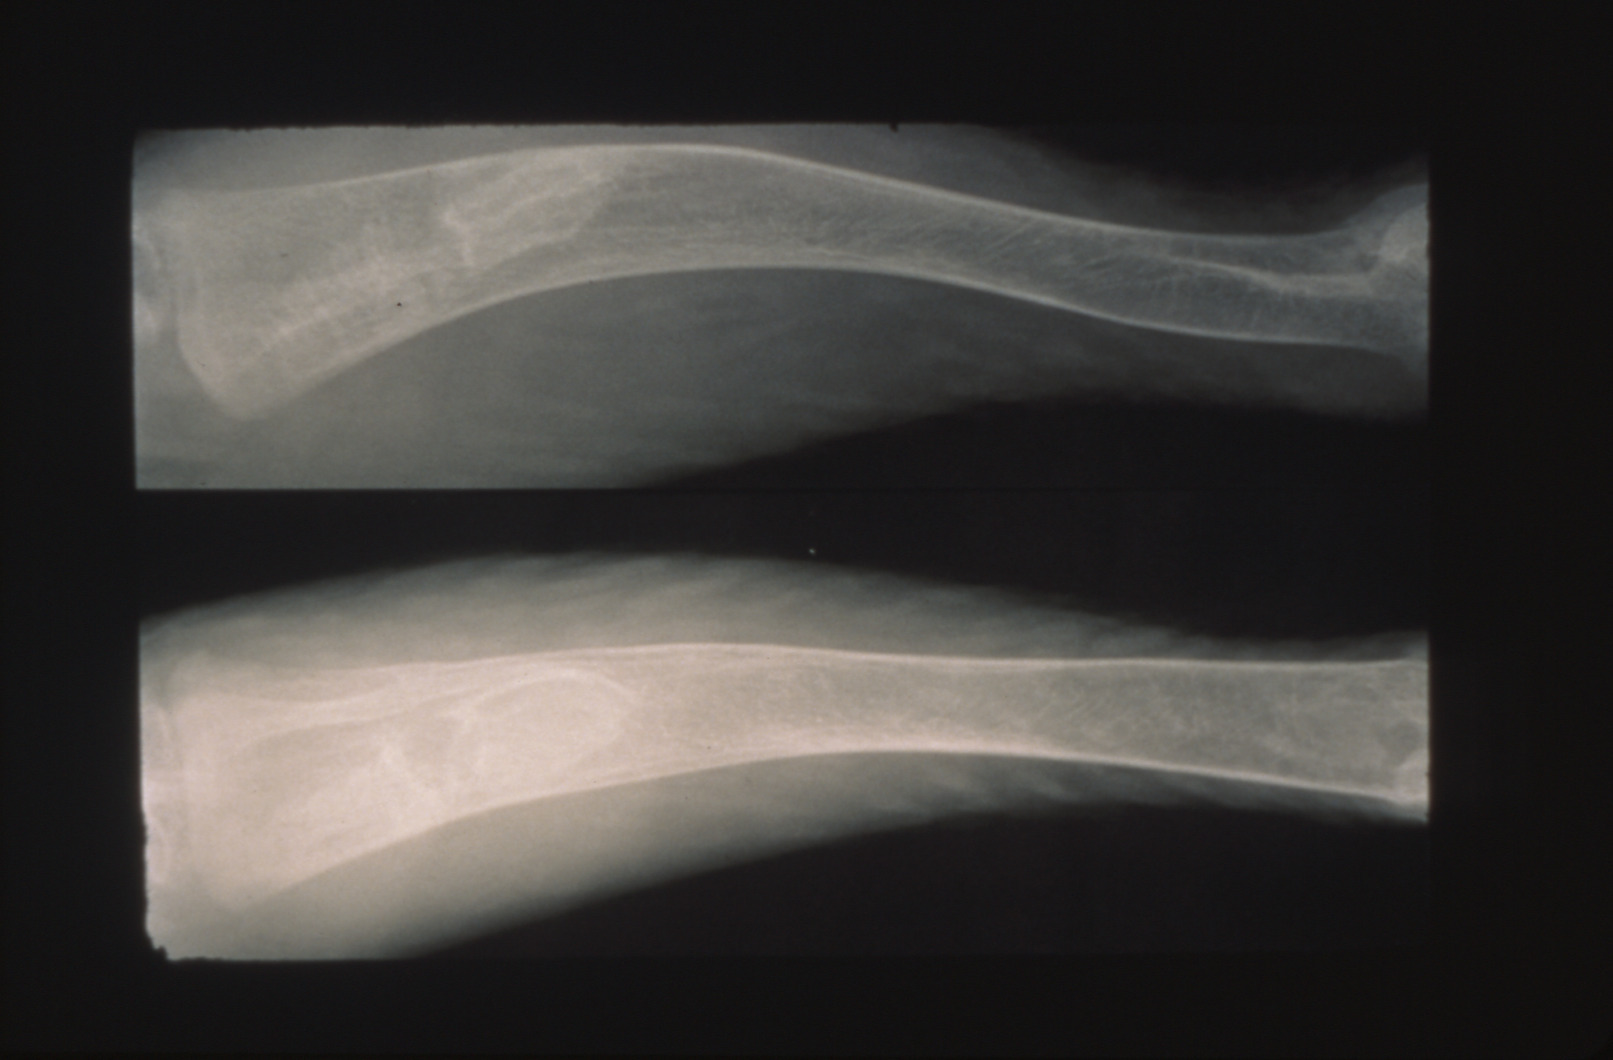

Tibial dyschondroplasia in domestic poultry (slide study set no. 6) Item Info

Tibial dyschondroplasia in domestic poultry (slide study set no. 6)

Avian medicine Poultry--Diseases Tibia

Slide Study Set #6, Tibial Dyschondroplasia, 2 sets (includes 34 color slides), 1975